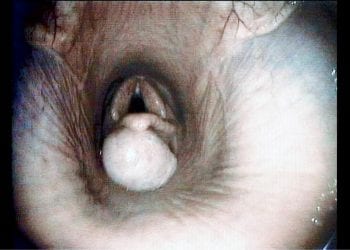

Figure 1. A videoendoscopic image demonstrating the large subepiglottic cyst at presentation. Note the secondary elevation of the epiglottis.

In this case, endoscopy of the upper respiratory tract was elected as the primary diagnostic procedure. This demonstrated a large (approximately 3cm diameter) well demarcated, mucosa-covered mass positioned ventral to the epiglottis and the epiglottic cartilage was dorsally deviated by the mass (Figure 1). A diagnosis of subepiglottic cyst was therefore made. Endoscopy of the trachea showed a small amount of food material on the tracheal walls. No abnormal respiratory secretions could be seen emanating from the sinus drainage angle on the left side.